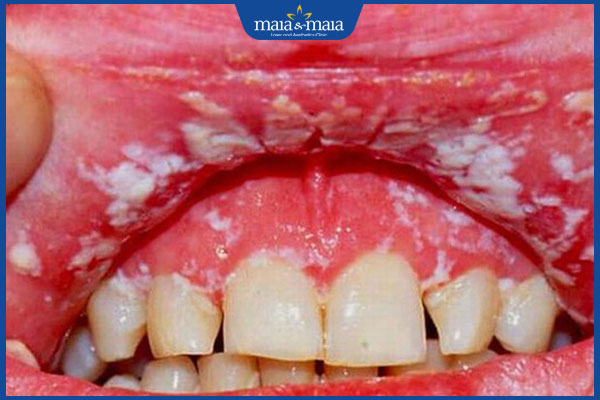

Nấm Candida ở miệng và họng sẽ gây những mảng trắng ngà/vàng nhạt bám ở lưỡi, má trong, nướu và vòm miệng. Niêm mạc miệng sẽ sưng đỏ, nóng rát và nếu vô tình chạm vào những mảng trắng dễ gây bong ra, chảy máu.

Ngoài ra còn có dấu hiệu nứt khóe miệng, khô miệng, mất vị giác hoặc trong miệng có cảm giác đắng/mùi kim loại. Nếu nấm Candida lan xuống họng và thực quản còn gây đau và khó nuốt, vướng thức ăn khi nuốt. Những hình ảnh nấm Candida ở miệng và họng để mọi người nhận biết gồm: